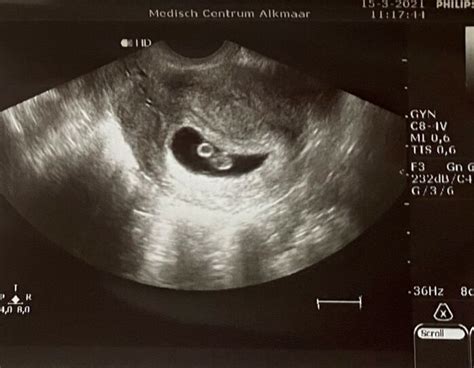

Een week later mocht ik me melden voor een eerste echo. De echoscopiste zag een vruchtzakje, maar geen kloppend hartje. Er werd gesuggereerd dat het misschien geen goede zwangerschap was, of dat ik nog heel pril zwanger was. Ondanks dat we dachten compleet te zijn, zat ik huilend in de auto.

Echo twee: een tweede vruchtzakje

Een week later zou ze weer kijken. Ze zag een kloppend hartje, maar het klopte niet heel erg snel. Ook zag ze een tweede vruchtzakje, dat leeg en substantieel kleiner was. Later zag ze zelfs een derde vruchtzakje, ook heel klein en leeg. De conclusie was dat het nog steeds geen goede zwangerschap leek te zijn, omdat het hartje te langzaam klopte. Met weer een nieuwe echo ging ik naar huis, vol onzekerheid.